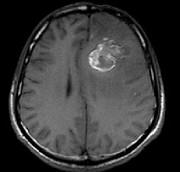

问题 男,34岁,3个月前行左额叶脑肿瘤切除术,近1个月又感头痛无恶心呕吐,近1周来又觉双下肢无力,并失语,请根据所提供图像,选择最可能的诊断()

选项 A.(左额叶)星形细胞Ⅱ级伴出血坏死(复发性) B.(左额叶)脑出血 C.(左额叶)海绵状血管瘤 D.(左额叶)动静脉血管畸形 E.(左额叶)脑肿瘤术后

答案 A